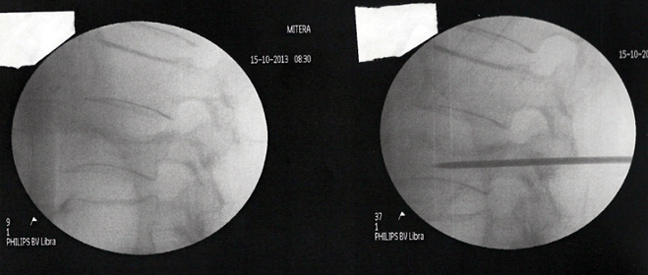

Η λύση αυτή ονομάζεται κυφοπλαστική. Χωρίς ανοικτή εγχείρηση, μέσω μίας χοντρής βελόνας (trocard) και παρακολουθώντας τη διαδρομή μέσω ακτινολογικής τηλεόρασης, εισάγεται μέσα στο σώμα του σπασμένου σπονδύλου ένα μπαλονάκι που φουσκώνει με νερό. Αναλόγως της πίεσης που ασκείται, ο σπόνδυλος διορθώνεται.

Στην κοιλότητα που δημιουργείται εισάγεται ακρυλικό τσιμέντο που όταν πήξει μετά μερικά λεπτά, καθιστά σταθερό και πάλι τον σπόνδυλο.

Η διαδικασία γίνεται με γενική νάρκωση και διαρκεί ¾ της ώρας. Μετά λίγες ώρες παραμονής στο νοσοκομείο, ο ασθενής επιστρέφει σπίτι του και από την επομένη κυκλοφορεί χωρίς πόνο, χωρίς κορσέ και χωρίς να γέρνει.